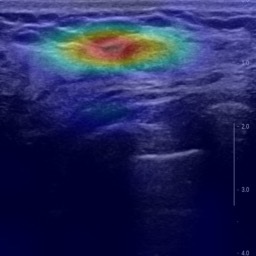

Ultrasonography is an important routine examination for breast cancer diagnosis, due to its non-invasive, radiation-free and low-cost properties. However, it is still not the first-line screening test for breast cancer due to its inherent limitations. It would be a tremendous success if we can precisely diagnose breast cancer by breast ultrasound images (BUS). Many learning-based computer-aided diagnostic methods have been proposed to achieve breast cancer diagnosis/lesion classification. However, most of them require a pre-define ROI and then classify the lesion inside the ROI. Conventional classification backbones, such as VGG16 and ResNet50, can achieve promising classification results with no ROI requirement. But these models lack interpretability, thus restricting their use in clinical practice. In this study, we propose a novel ROI-free model for breast cancer diagnosis in ultrasound images with interpretable feature representations. We leverage the anatomical prior knowledge that malignant and benign tumors have different spatial relationships between different tissue layers, and propose a HoVer-Transformer to formulate this prior knowledge. The proposed HoVer-Trans block extracts the inter- and intra-layer spatial information horizontally and vertically. We conduct and release an open dataset GDPH&GYFYY for breast cancer diagnosis in BUS. The proposed model is evaluated in three datasets by comparing with four CNN-based models and two vision transformer models via a five-fold cross validation. It achieves state-of-the-art classification performance with the best model interpretability.